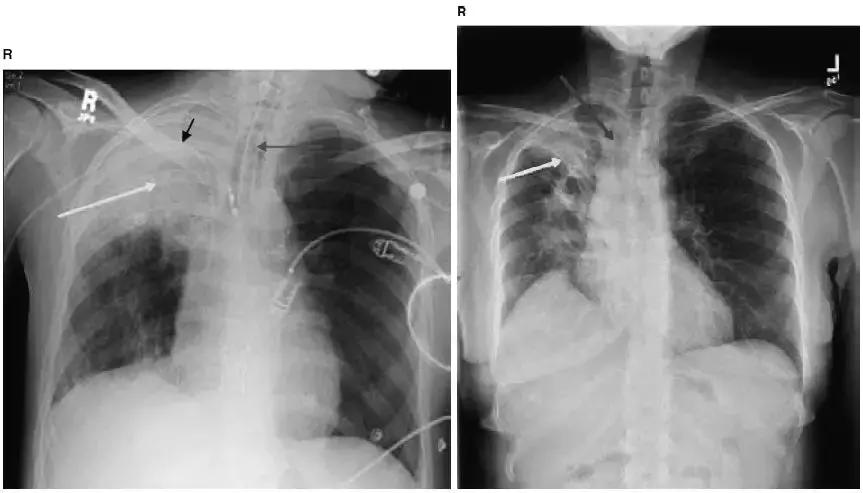

图4-21 A.正位胸片:气管旁(蓝箭头)、主肺动脉窗(黄箭头)和肺门淋巴结肿大(紫箭头);B.侧位胸片:肺门淋巴结肿大(紫箭头)

图4-23 Ⅱ期结节病胸片:A.正位胸片显示肺门淋巴结肿大(黑箭头)和肺实质改变;B.侧位片显示肺门淋巴结肿大(黑箭头)和肺实质改变